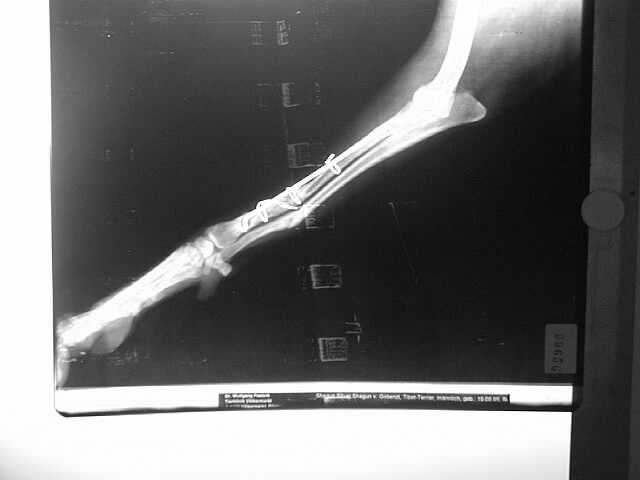

Elle-Speichen-Fraktur

paraossäre Klammer-Cerclage-Stabilisierung